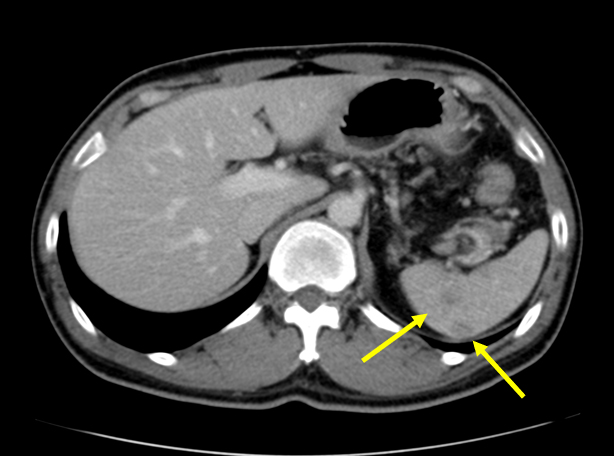

No. 154 症例4:30歳代男性

【画像所見まとめ】

• 脾多発腫瘤、脾門部多発リンパ節腫大

• 肝、脾